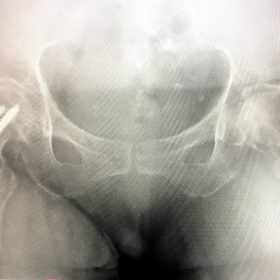

Κατάγματα Ισχίου